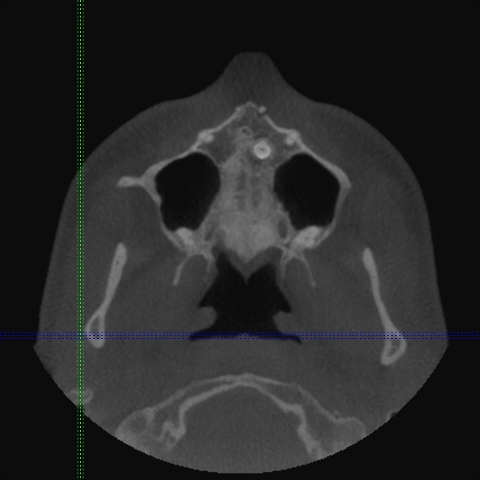

Za razliko od običajnih CT-naprav, kjer rentgenski snop prodira skozi tkivo v ravninah in slika nastane z obdelavo vseh »rezin«, ki so različno narazen (običajno 1 do 3 mm), pri CT-napravah s stožčastim snopom detektorji sprejemajo stožčast snop – podatki dajo sliko prostornine in ne samo ravnine. Naprave so precej manjše, pacientu ni treba ležati, odmerek sevanja, ki ga prejme pacient, je okrog 50-krat manjši, kot pri običajnih CT preiskavah, slika trdih tkiv (torej kosti in zob) pa je neprimerno ostrejša (slike 2, 3, 4).

Slike 2, 3, 4: Posnetki CT-ja s stožčastim snopom. Položaj nadštevilčnega zoba je jasno prikazan v vseh treh ravninah, lepo se vidi, da zob s krono sega v nosno votlino. Zob je mogoče natančno izmeriti.